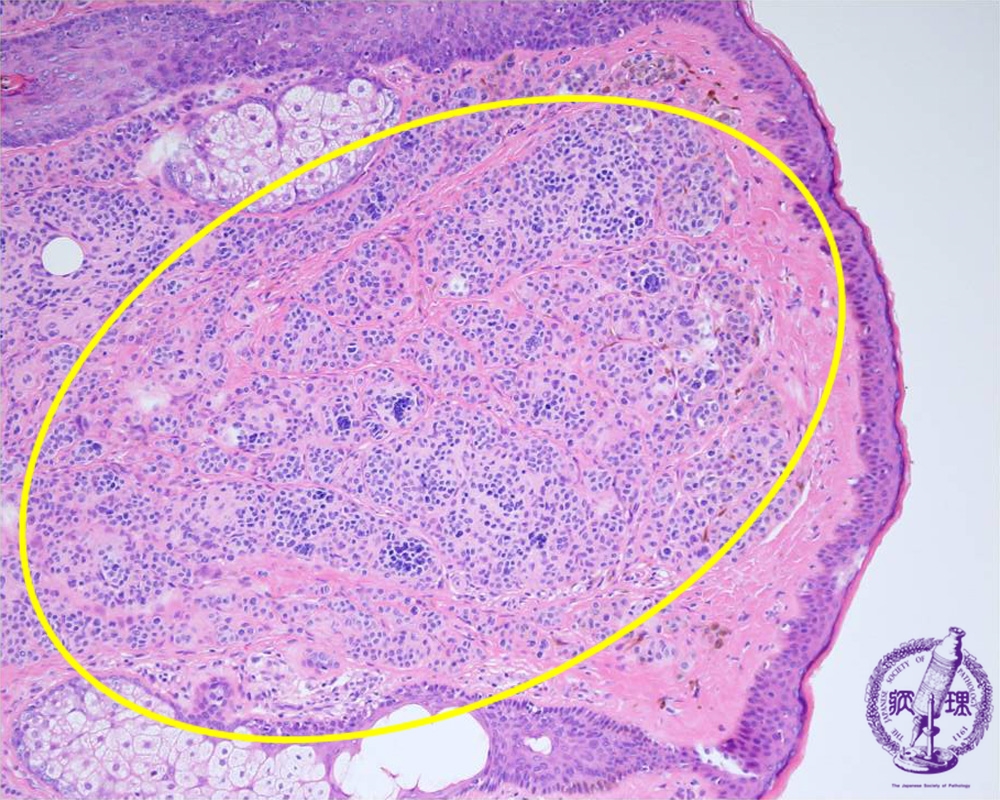

- (5)Melanocytic nevus (intradermal, junctional, compound)

Microscopic findings: Nevus cells scatter in the dermis (inside of a circle). Nevus cells are suggested to be induced by incomplete differentiation. They are related to the melanocytes and Schwann cells.